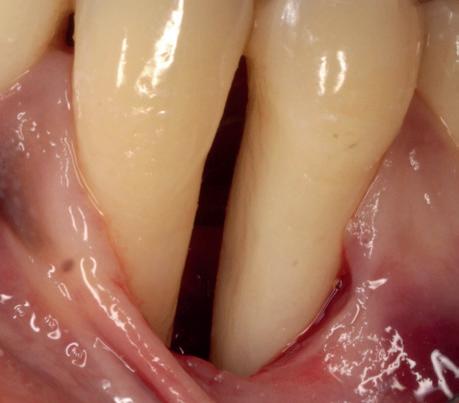

De flap en graft worden met poly-propelene 6.0 hechtingen gefixeerd. De tijdelijke reconstructie wordt herplaatst (foto 17-20).

Na 4-6 weken kan het aangebrachte healing abutment worden vervangen door een tijdelijk abutment. Deze wordt aan de kunststof reconstructie verbonden om zo de gingiva ter plaatse van de 22 te vormen. Zo lijkt het of er geen implantaat maar nog steeds een wortel aanwezig is, wat het esthetisch eindresultaat ten goede zal komen (foto 21-23). Vanaf 4-6 maanden ziet het weefsel er gezond uit. Nu kan met de uiteindelijke restauratiefase worden gestart (foto 24 en 25).

gewonnen. De wond kan na het plaatsen van een healing abutment primair gesloten worden (Afbeelding 3a-3d).

In afbeeldingen 4a-c is het resultaat drie maanden na het plaatsen van het implantaat te zien. De genezing is volledig en de verwijzer kan de suprastructuur vervaardigen (afbeelding 4a-4c).